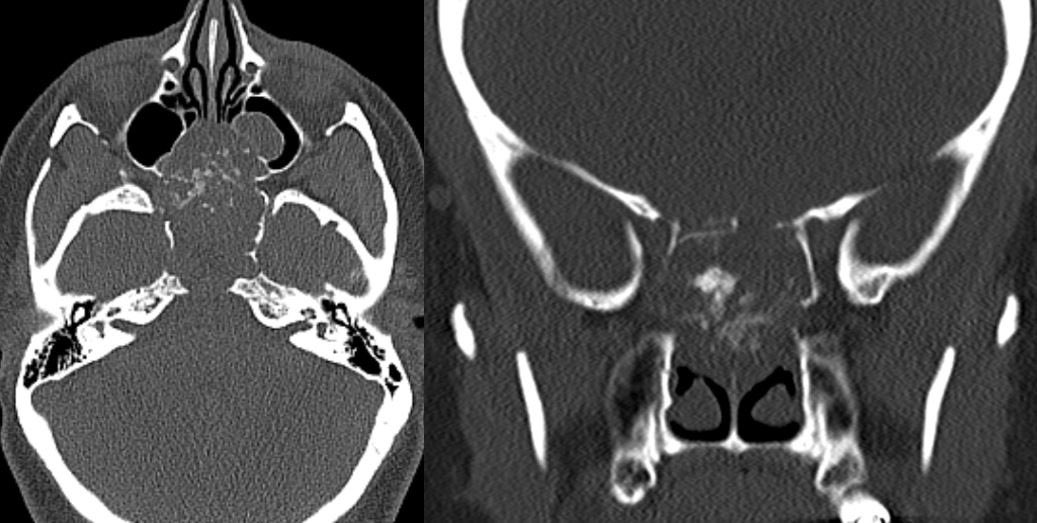

11 yo male with history of growth retardation and myopia presents with bradycardia and loss of consciousness.